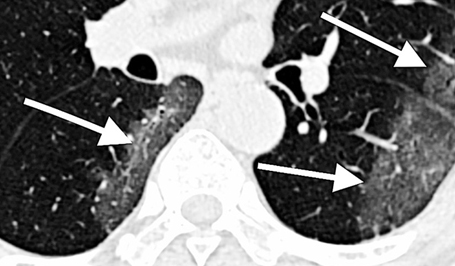

Dr. Scott Sigman, principal investigator has reported positive results from the first-ever use of laser therapy to treat a Covid-19 pneumonia patient.

Published in the American Journal of Case Reports, the article shows that after supportive treatment with Photobiomodulation Therapy the patient's respiratory indices, radiological findings, oxygen requirements and outcomes improved over several days and without the need for a ventilator. The patient in the report is part of a randomized clinical pilot trial involving 10 patients with confirmed Covid-19.